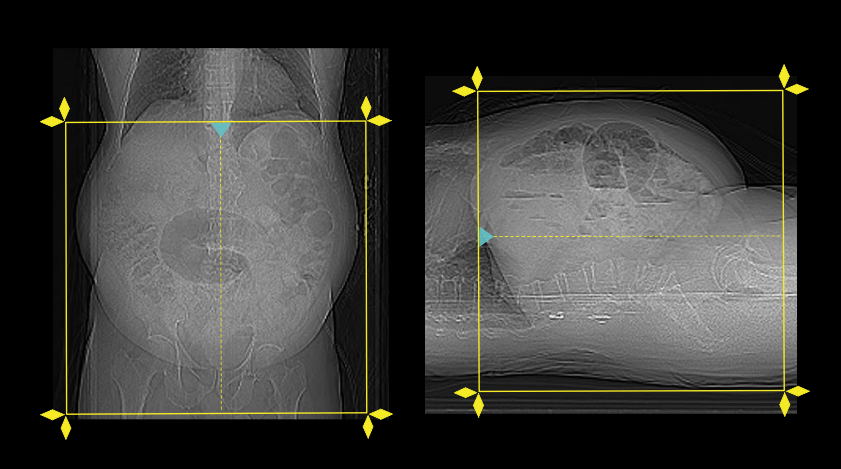

- Position the patient in supine and feet first on the imaging couch.

- Center the scanning area in the scanner iso-center [6].

Explanation: this reduces overall radiation exposure and increases image quality.

- Raise both hands above the head and place a positioning aide under them.

Explanation: hands beside the trunk give streak artifacts and increase radiation exposure.

- Plan the scan starting point at the nipple level.

- Plan both pre-contrast and excretory phases to cover from dome of the diaphragm to a level just below the ischial tuberosities.

- Plan all pre-contrast, nephrogenic and excretory phases to cover from the mid-diaphram to a level below the ischial tuberosities.

- Plan corticomedullary phase to cover from the mid-diaphragm to the iliac crest.